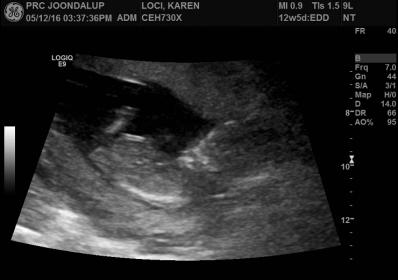

3rd,4th,5th and 6th are 12 week shots